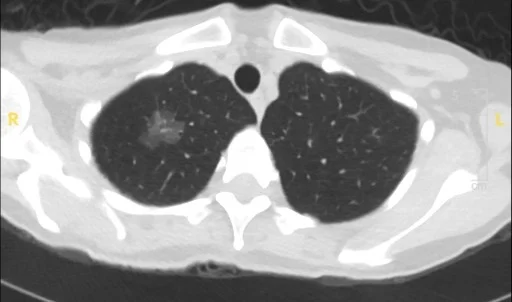

Those subtypes look different from one another on CT scans. “Indolent lesions tend to be characterized by nodules with a ground-glass appearance. Nodules that are more aggressive tend to have a solid appearance on imaging studies,” Dr. Powell says. “In the past, the management approach to those two types of nodules would have been the same. Now that we can distinguish subtypes based on imaging, we’re more comfortable following the low-risk lesions and intervening only when there has been a significant change.”

CT image of ground-glass and part-solid nodules taken in 2019

Same patient rescanned in 2023

Importantly, research also suggests that this watch-and-wait approach doesn’t increase risk to patients. “I’ve been monitoring some patients for 15 years with no changes to their indolent tumors,” Dr. Powell says. “And we’ve learned that when we do detect a change on imaging, we have sufficient time to intervene.”